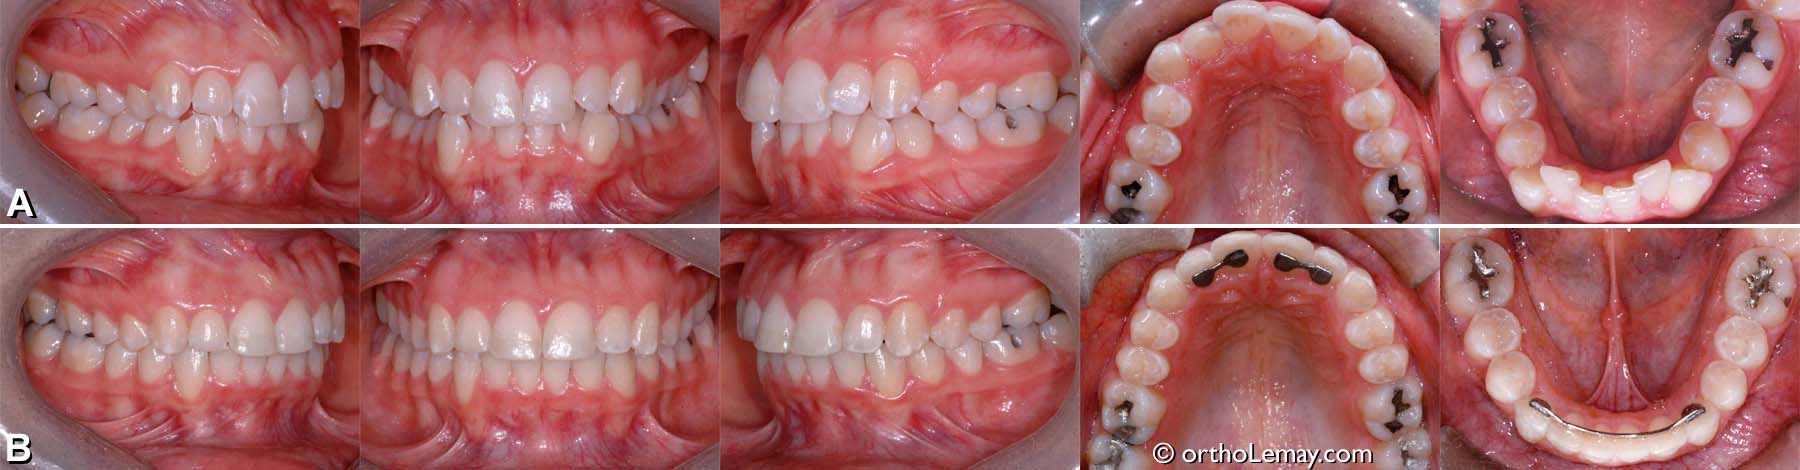

Exemple de traitement de malocclusion classe 1 (18)

(A) Malocclusion dentaire classe 1, overbite excessif, manque d’espace et déviation des lignes médianes.

(B) Après le traitement, le surplomb est corrigé, les lignes médianes alignées et les dents logées convenablement dans les arcades.